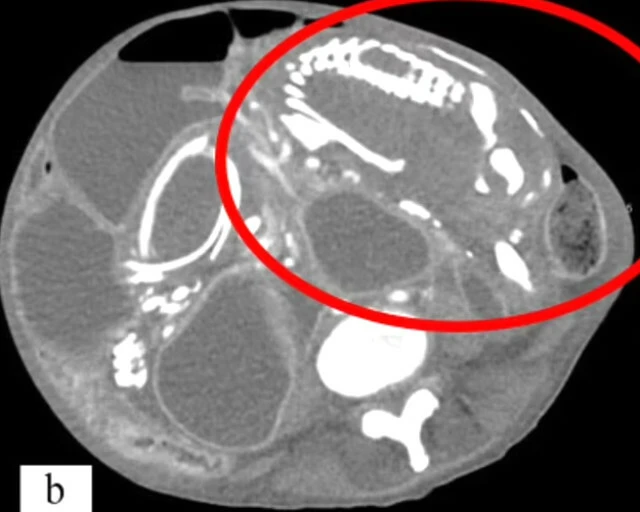

New York'tas hayatını idame ettiren 50 yaşındaki bir kadın, şiddetli karın ağrısı şikayetiyle doktora başvurdu. Doktorlar, incelemelerini tamamladıklarında ise oldukça ilginç bir durum ile karşı karşıya olduklarını fark ettiler. Kadının 9 yıl önce rahmi yerine bağırsaklarında bir cenin meydana geldi ve bu cenin zamanla taşa dönüştü. Taşlaşan cenin, kadının bağırsaklarını tıkadı ve zamanla vücut besinleri emmemeye başladı. Uzun süre besinsiz kalan vücut iflas etti ve kadın hayatını kaybetti.

Şu ana kadar 300 kez meydana gelen vakada, cenin rahimde değil bağırsaklarda bir süre geliştikten sonra ölüyor. Zamanla taşa dönüşen cenin, kişinin sağlığını ciddi şekilde tehlikeye atıp bazı durumlarda ölüme sebep oluyor.